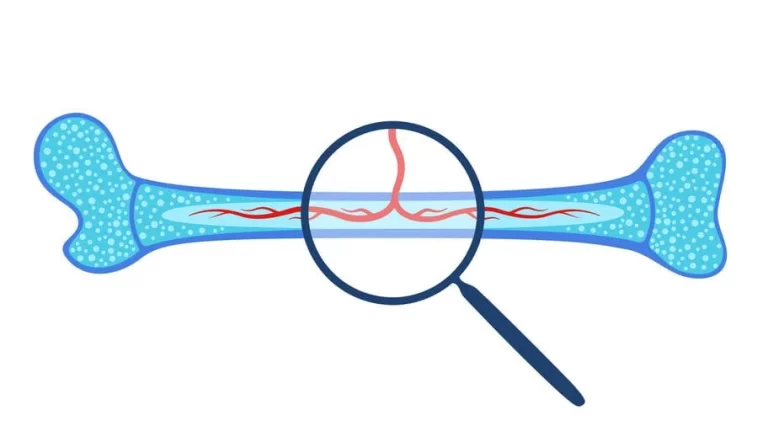

يهدف زرع نقي العظم إلى استبدال النخاع العظمي المتضرر نتيجة الإصابة ببعض الأمراض، مثل: سرطان الدم، وفقر الدم اللاتنسجي ، وقلة الصفيحات المناعية ، وبعض الأمراض الوراثية المختلفة كالثلاسيميا والورم النخاعي المتعدد . طريق زرع نقي العظام زرع نقي العظامإحدى…